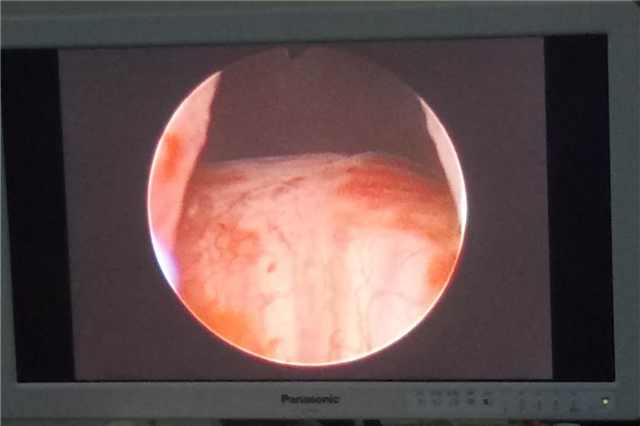

术中,刘红耀主任结合电切镜观察,最终选用41B前列腺扩裂导管,电切镜观察12点位扩开充分,用时15分钟就顺利完成手术。术后,医护人员做压腹排尿实验,患者排尿通畅,尿线已经与正常人无异。

术后,患者尿道扩开充分